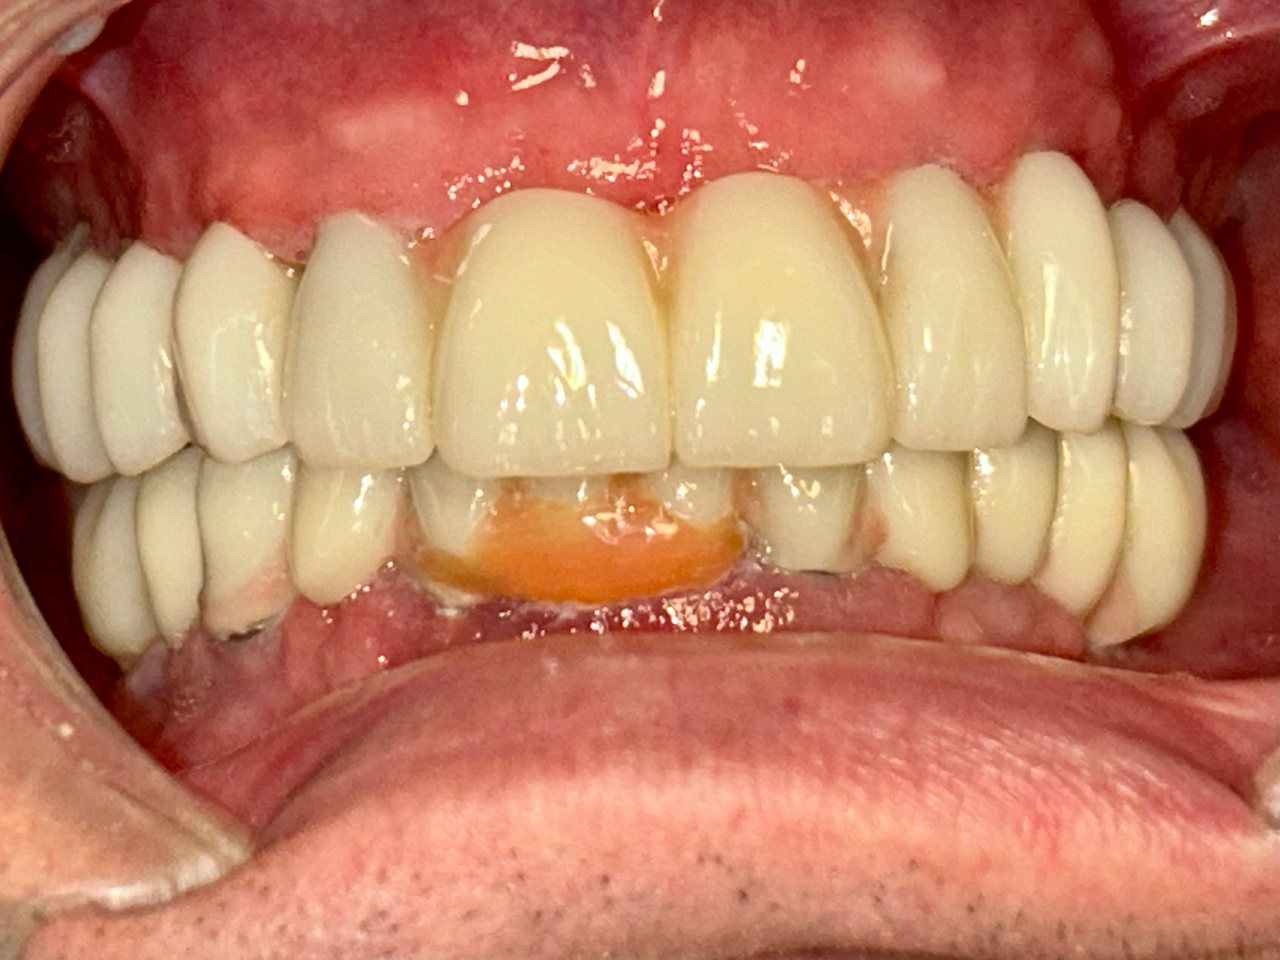

Teljes alsó,felső állcsont helyreállítása azonnal

terhelhető implantátumokkal és porcelán hidakkal.

Rágófunkció esztétikus helyreállítása azonnalterhelhető svájci IHDE implantátumokkal és porcelán koronákkal.

A régóta fennálló foghiány és a mozgó fogak miatt a páciens nem tudott jól rágni és harapni, illetve mosolyogni sem mert már jó ideje. A leggyorsabb és a legesztétikusabb megoldás az ilyen esetekre az IHDE azonnal terhelhető implantátumok behelyezése, és az azokra rögtön elkészített porcelán koronák elkészítése.

A teljes munka - az implantáció, a végleges koronák elkészítése - 5 munkanapot vett igénybe.